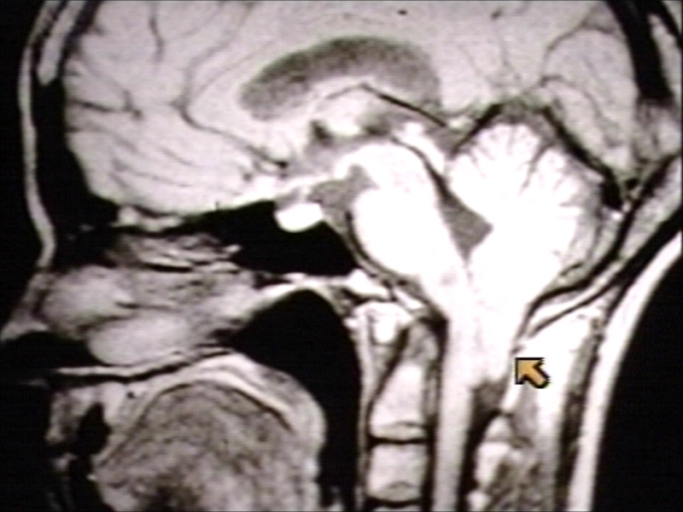

Симптомы аномалии арнольда киари

Симптомы аномалии арнольда киари 107 фотографий